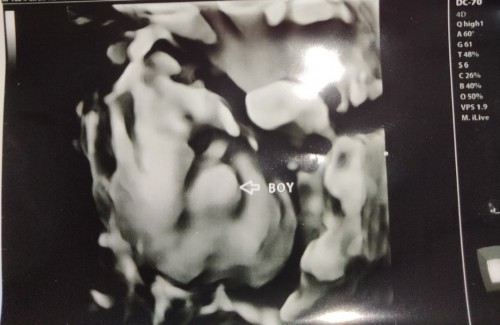

kenal jantina baby

hai smue sye nk tnye kalau scan 5D dokter ckp jantina boy memng tepat ke boy..was2 sikit..siape ade pnglmn buat 5d

hi sis nk tnya . yg ni scan 5d ke? mmg warna hitam putih eh.bukan berkaler?